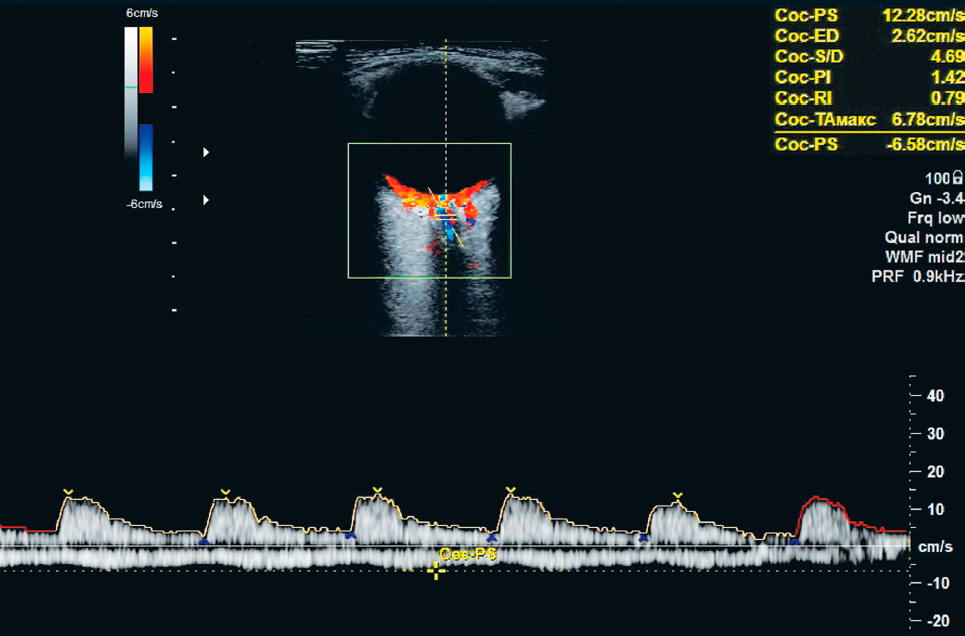

The mean age of the patients was 68.0 ± 8.4 years. All procedures were performed by the same surgeon. The surgical procedures were performed under local anesthesia (three instillations of 0.4% oxybuprocaine eye drops within 30 minutes before surgery). IOP in the phacoemulsification system was set considering the height of the operating table in each case. For each procedure, different IOP values (40 and 60 mmHg) were set for procedure steps in the phacoemulsification system. Blood pressure (BP) at the brachial artery and peripheral blood oxygen saturation were monitored in all patients using Draeger Vista 120 (Draeger, Germany). Color Flow and Pulsed Wave Doppler modes on a Logiq S8 multi-purpose diagnostic ultrasound system (GE, USA) were used to assess CRA blood flow with measurement of peak systolic (PSV) and end-diastolic velocity (EDV) and peripheral resistivity index (RI). An US probe was positioned without compressing the eyeball using a sterile US contact gel to obtain transpalpebral images of the optic nerve in the center of the scanner monitor. Then, in the center of the echogenic shadow of the retrobulbar nerve part, 1.0–3.0 mm from the posterior pole, the CRA was identified in the CFD mode by its red color (blood flow toward the transducer) and the central retinal vein by blue color (blood flow away from the transducer) [5]. As the CRA is located near the central retinal vein, Doppler images of these vessels are recorded simultaneously (arterial are above the baseline, venous are below the baseline) (see Fig. 1).

Fig. 1. Eye and orbit color flow and pulsed wave Doppler images: blood flow in the center of the optic nerve shadow near the posterior pole represents the central retinal artery (CRA) and central retinal vein (CRV). Doppler images of blood flow in the CRA (above the baseline) and CRV (below the baseline). CRA blood flow parameters: PSV 12.28 cm/s; EDV 2.62 cm/s; RI 0.79.